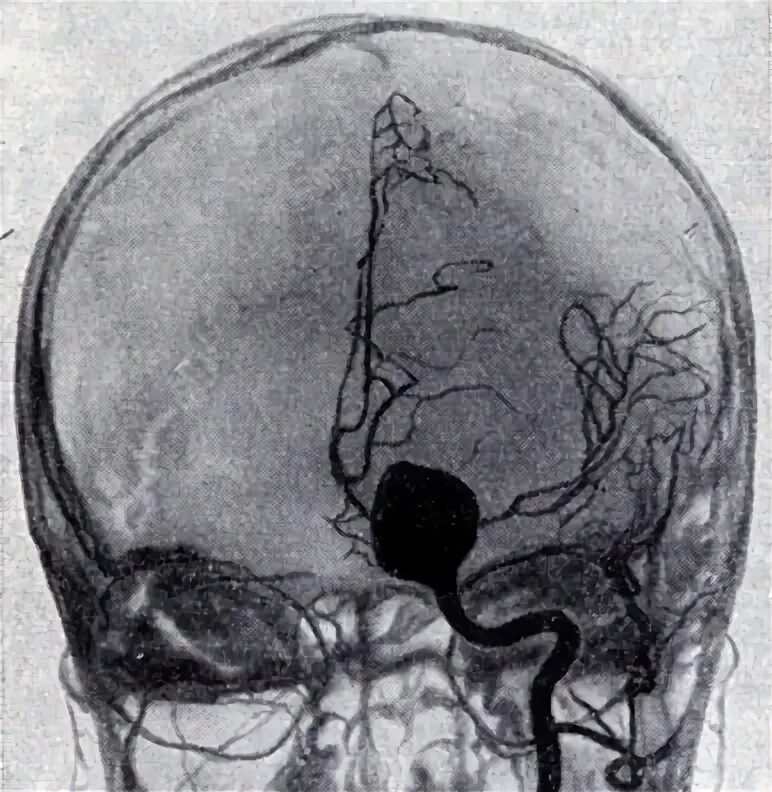

Мешотчатая аневризма внутренней